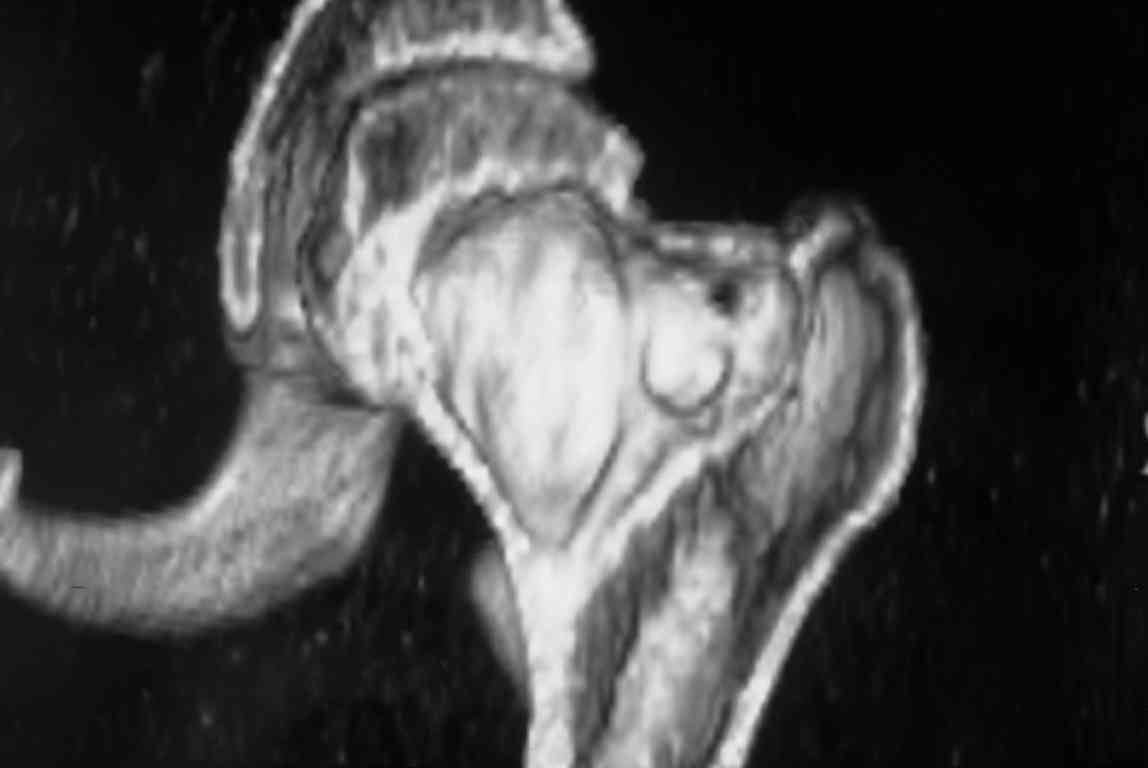

Больная Л., 23 года. Из анамнеза:со слов больной в 2006 г. появились боли правой н/конечности, обратилась поместу жительства к хирургу, было выполнена МРТ поясничного отдела позвоночника,назначено физиолечение. Через 2 месяца боли прекратились, через 4 месяца рецидив болевого синдрома. С 2006 – 2010 проводилось консервативное лечение по поводу остеохондроза поясничного отдела позвоночника. В октябре 2010 г. боли усилились. Выполнены Ro и КТ правого тазобедренного сустава, выявлен очаг патологической перестройки. Была направлена на консультацию в УНИИТО. В УНИИТО виюне 2011 г. поставлен дифференциальный диагноз между фибромой, солитарной костнойкистой и гигантоклеточной опухолью.

Клиника и течение заболевания похожи на однокамерную кисту. Больная молодая, желательно сохранить собственную головку. Надо спешить с операцией, иначе скоро произойдет перелом через тонкую стенку. Во время операции внутри будет пустота и небольшое количество жидкой крови.